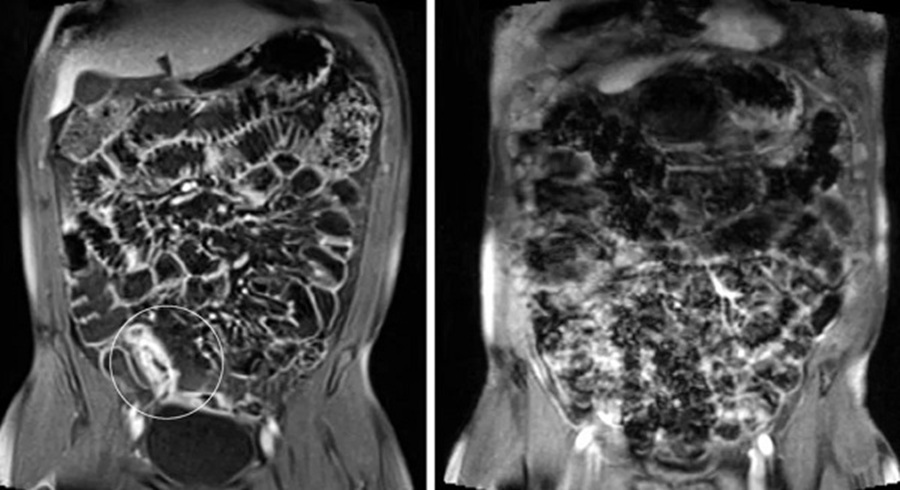

МРТ кишечника позволяет врачу получить детальную информацию о состоянии стенок кишечника, просвета, окружающих мягких тканей и лимфатических узлов. Благодаря высокой чувствительности к изменению структуры тканей, этот метод выявляет даже начальные стадии патологий, которые могут быть не видны на УЗИ или рентгенологических снимках. Исследование позволяет оценить толщину и структуру стенки кишки, наличие воспалительных очагов, отёка, стриктур, рубцовых сужений, опухолей, свищевых ходов и иных отклонений от нормы.

На МРТ хорошо визуализируются воспалительные изменения при болезни Крона или язвенном колите — можно не только зафиксировать участок поражения, но и оценить степень активности воспаления. Также процедура позволяет увидеть наличие инфильтратов, инородных тел, жидкостных скоплений, участков некроза и других осложнений. При подозрении на опухолевые процессы МРТ показывает форму, размеры и границы образования, а также вовлечение в процесс близлежащих структур, что особенно важно для выбора тактики лечения.